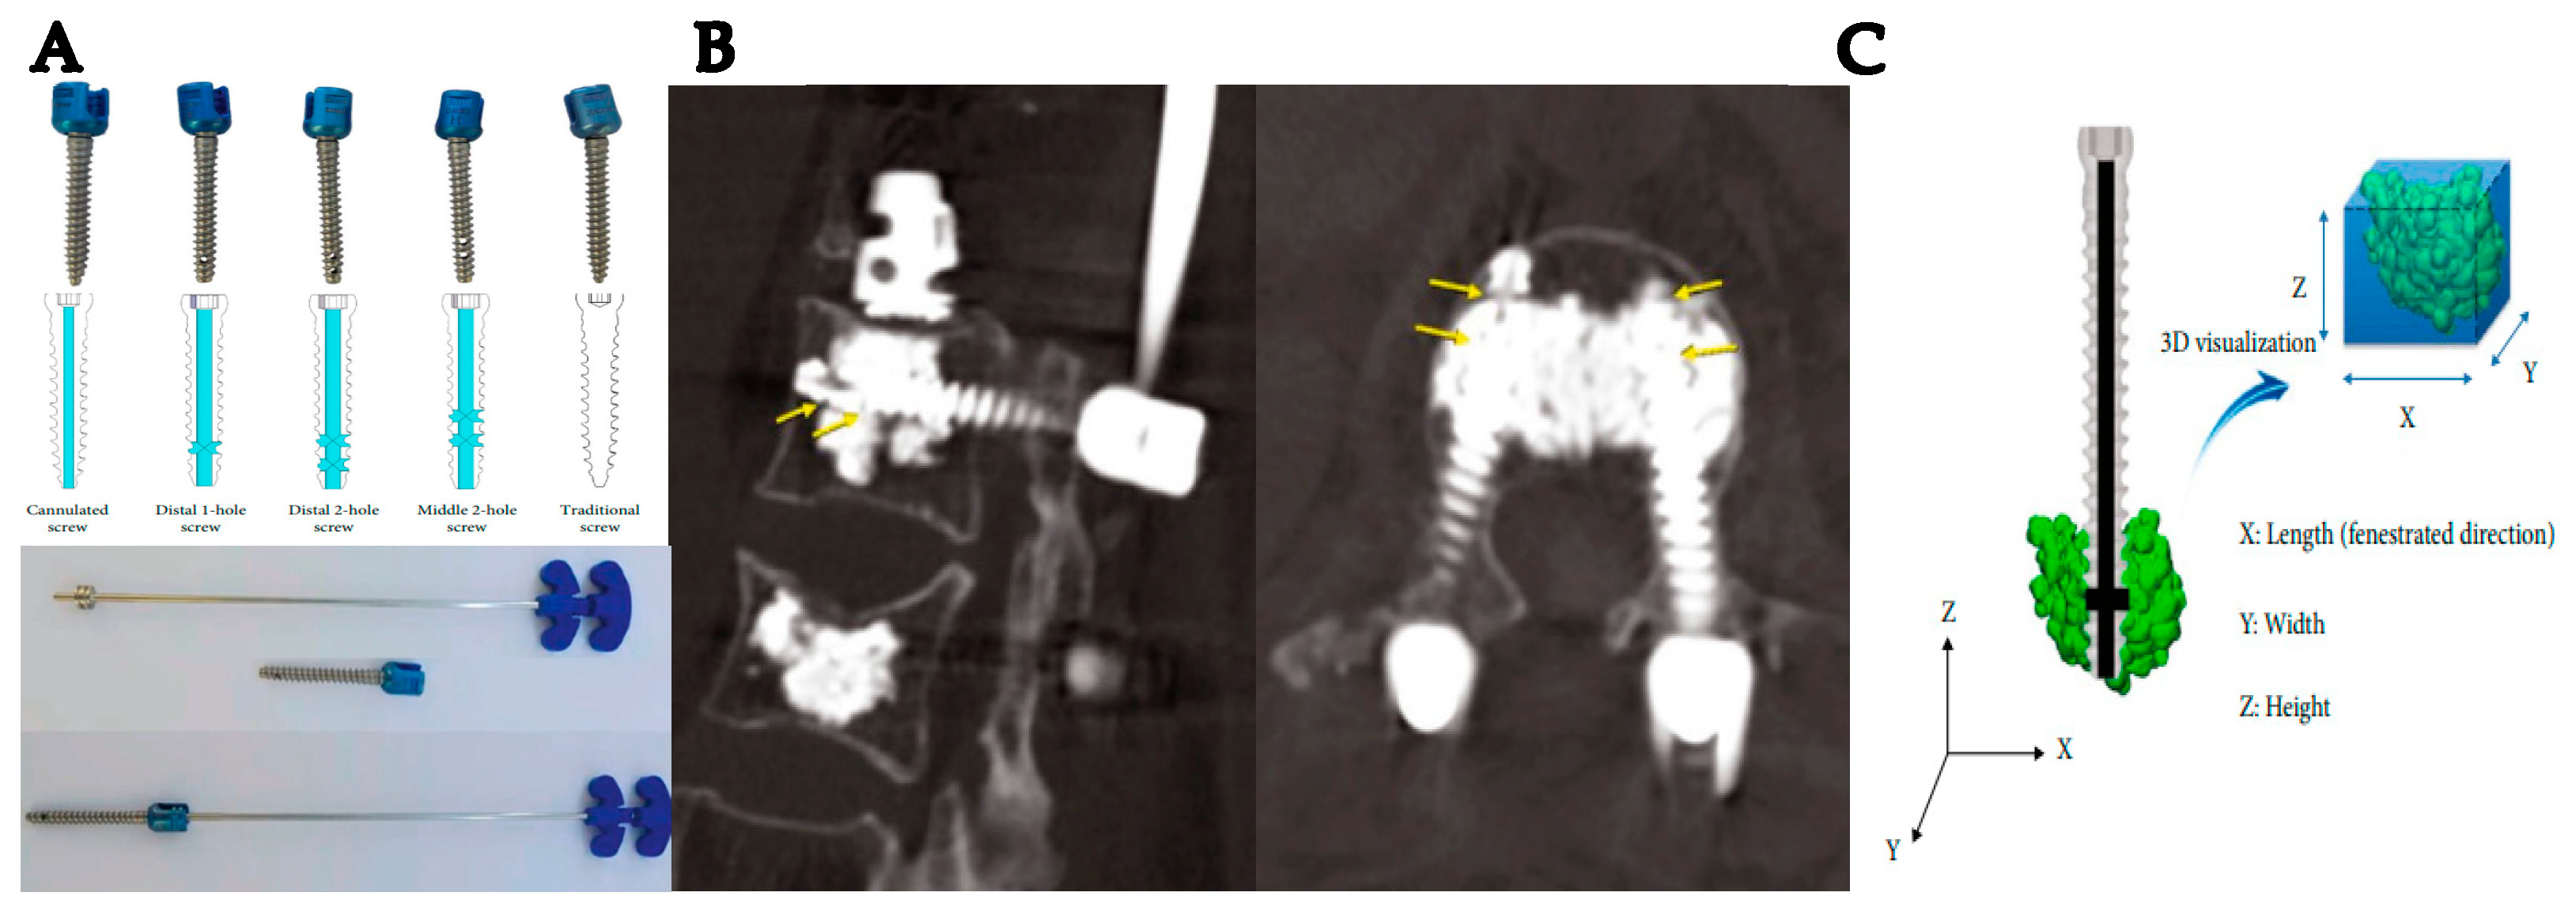

PMMA is known as acrylic cement, providing superior osteointegration, good tensile properties, good flexural rigidity, and the absence of interim fibrous tissue around cemented elements [53,54]. However, PMMA is limited by the potential for microfractures, the release of cement particles (such as methacrylate monomers [MMA]) and heat, localized foreign-body reactions, and limited biological response [53,54]. The release of MMA can lead to hemodynamic effects that may include reductions in blood pressure and oxygen saturation levels [18]. PMMA is a versatile substance utilized in orthopedics, dentistry, and ophthalmology. PMMA is used in orthopedics as a permanent bone substitute to treat pathologic fractures and is also used in internal fixation plates, spinal fracture fixation, and hip arthroplasty [69,70]. The most important feature of PMMA is its ability to be shaped into the specific forms required by implants or polymerized in situ while the patient is undergoing surgery. The polymerization process lasts 6 to 7 min. When PMMA is used as a cement to secure prostheses to the bone, bone adhesion is ensured by including HA particles in the polymer, resulting in a uniform load transmission from the implant to the bone [71,72]. For fragility fractures, such as in vertebroplasty or kyphoplasty, PMMA injections provide increased stability and decreased pain [73,74,75]. The extravasation of PMMA to the spinal canal and foramen is a major potential problem that may affect the spinal nerve root [74]. In response to these concerns, there has been recent interest in using cannulated fenestrated screws in combination with PMMA cement for surgical treatment of osteoporotic vertebral fractures [76]. Recently, various bone cement cannulated fenestrated screws for osteoporosis patients have been developed. For example, The Iliad™ pedicle screw system (Medyssey Co., Ltd., Jecheon, Republic of Korea), which is a cannulated fenestrated screw system, underwent a study regarding the optimal design of cement-augmented screws to reduce cement leakage-related complications (Figure 2) [73]. The modified design of the fenestrated screw and the application of the suggested cement injection pressure resulted in minimal spinal canal leakage and easy access.

Figure 2.

(A) Cement screw design and cement injector in the Iliad™ pedicle screw system. (B) The guide arrow indicate the side hole of fenestrated screw in clinical computed tomography. (C) Three-dimensional analyses of cement distribution [73].

Moreover, we experienced an unexpected gap between the basic scientists and clinicians in the development of improved design of fenestrated pedicle screws for cement augmentation. The most biomechanically sound design of fenestrated screws could not be applied in real osteoporotic patients in actual clinical practice, due to high risk of cement leakage into the spine canal, which could result in neurologic compromise. This gap between safety and efficiency will be a common phenomenon for all other biomaterial and biotechnologic devices. To bridge this gap and develop clinically applicable biomaterials, numerous studies on biomaterials in a physiological environment, as well as improved interactions between clinicians and basic scientists, would be necessary. Rather than comprehensively dealing with biomaterials at the basic science level, this review deals with the view of biomaterials from the perspective of a clinical spinal surgeon.